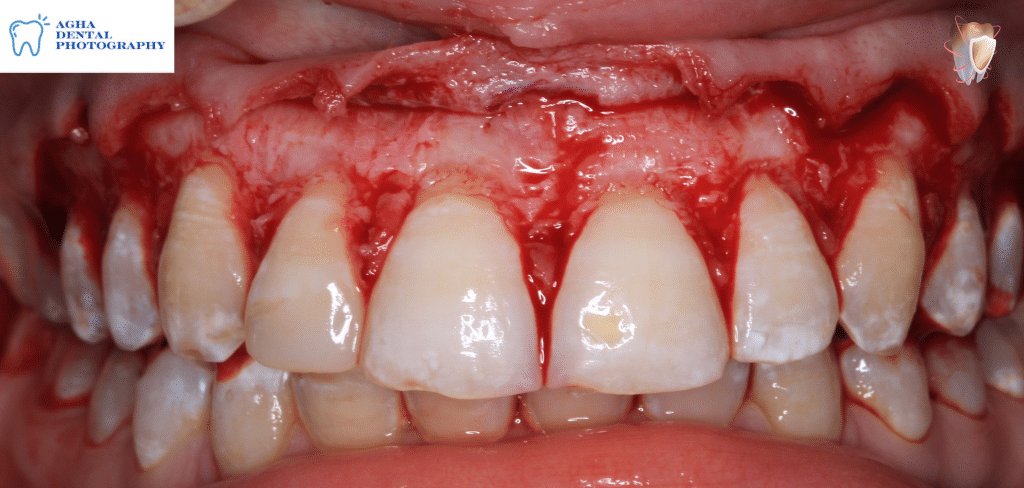

External bevel gingivectomy

Removal of excised tissues using a sharp scaler

After finishing gingivectomy

Elevation of a full thickness envelope flap revealing an irregular & thick labial bony